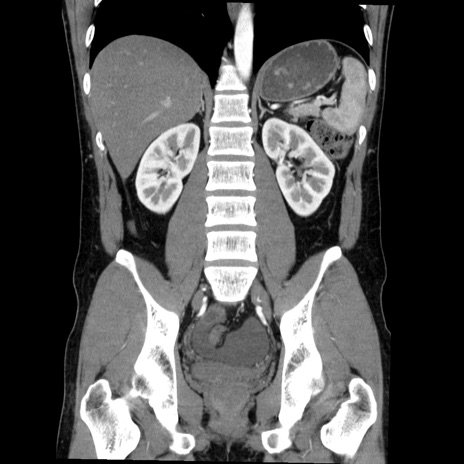

症例36(冠状断像)

【症例】20歳代 男性

【主訴】心窩部痛

【現病歴】今朝より上腹部痛あり。一旦軽快していたが再度出現したため救急要請。昨日夕に白身の魚を含む刺身を食べた。

【身体所見】BP 136/89mmHg、HR 74/min、BT 37.0℃、腹部:膨満、軟、心窩部に圧痛あり。反跳痛なし、筋性防御なし、腸雑音やや亢進あり。

【データ】WBC 17700、CRP 0.48